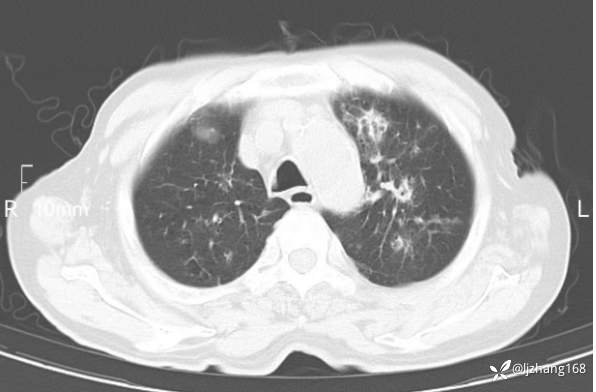

老年男患,咳嗽,气短,双肺多发间质性病变,何种感染?(有结果)

辅助检查:胸部CT:双肺肺气肿,间质性病变,血气分析:PH 7.413, PCO2 29.2mmHg, PO2,81.8mmHg,乳酸 3.3mmol/1,剩余碱-4.0mmol/1,HC03 18.8mmol/1。全血超敏C反应蛋白:超敏C反应蛋白 135.60 mg/L、 白细胞 14x19^9/L,中性粒细胞11.6x10^9/L。